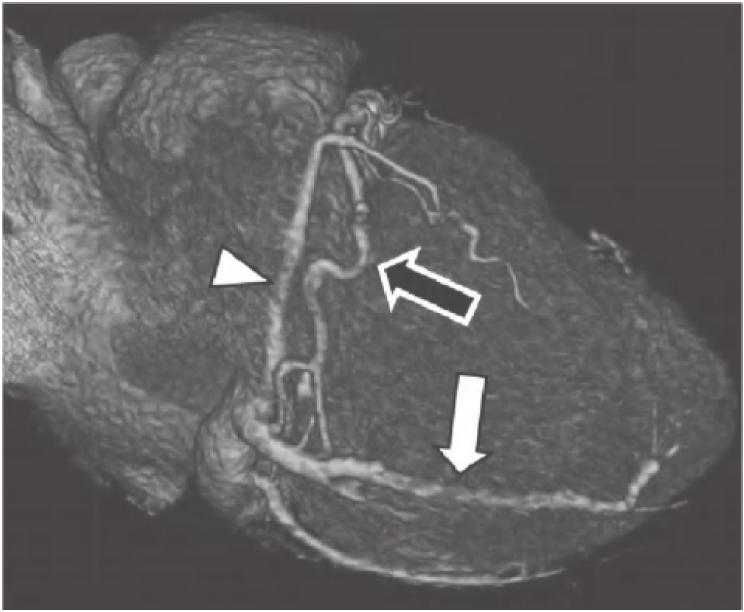

图13-4 RCA优势型,RCA绕过右心缘,在RAVG的下方发出后降支(箭),并走行于后室间沟(虚线)。心中静脉(箭头)也在后室间沟内走行

RCA.右冠状动脉;RV.右心室;LV.左心室